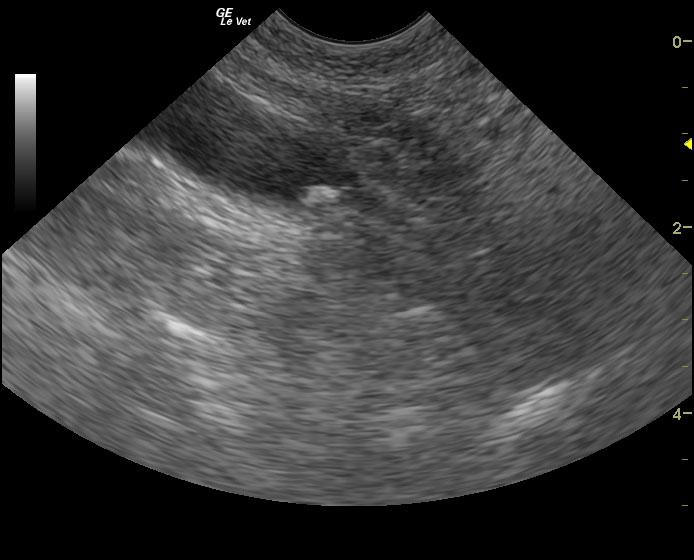

The patient is a feline DSH, SF, 17 years old. Clinical exam findings: Acute onset weakness and fever on PE (105 F), client reports hyperexia and acute onset stranguria, pollakiuria. Recently increased Methimazole due to ongoing elevation in T4. Recent COHAT with extraction, mild suture reaction, no intra-oral inflammation currently. History of suspected pyelonephritis treated with 6 week course Clavamox with 2 negative cultures. Altered CBC/Chem/UA values: Today- CBC- WBC= 24 (5.5-19), Lym= 1.26 (1.5-14), Neut= 21.4 (2.5-14). Chemistry: BUN= 57 , Creatinine= 3.4 (0.3-2.1). Systemic BP WNL.

The patient is a feline DSH, SF, 17 years old. Clinical exam findings: Acute onset weakness and fever on PE (105 F), client reports hyperexia and acute onset stranguria, pollakiuria. Recently increased Methimazole due to ongoing elevation in T4. Recent COHAT with extraction, mild suture reaction, no intra-oral inflammation currently. History of suspected pyelonephritis treated with 6 week course Clavamox with 2 negative cultures. Altered CBC/Chem/UA values: Today- CBC- WBC= 24 (5.5-19), Lym= 1.26 (1.5-14), Neut= 21.4 (2.5-14). Chemistry: BUN= 57 , Creatinine= 3.4 (0.3-2.1). Systemic BP WNL. U/A- U.S.G.= 1.020, NSF, sent out for culture. B/W performed a week ago- CBC WNL (WBC= 9, Neut= 5.8), Chemistry- BUN= 42, Creatinine = 2.2.